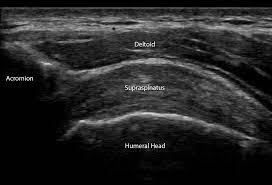

These changes are visible in an ultrasound scan.

Second, diagnose properly. With an ultrasound scan you can detect the problem.